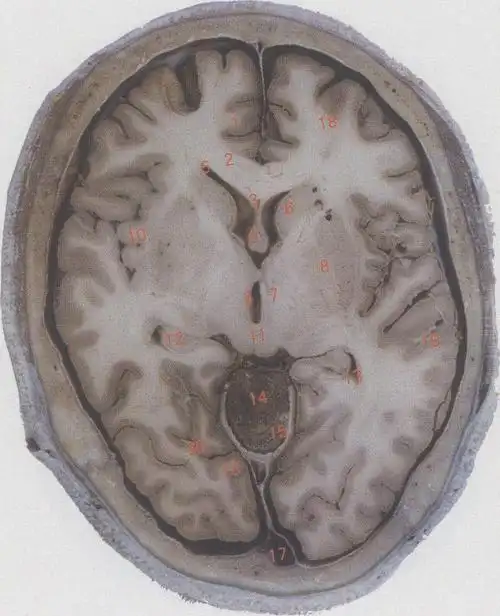

脑的水平切面图.中枢神经包括位于颅腔的脑和位于椎管的脊髓.

脑的水平切面

(图) 第三脑室水平切面